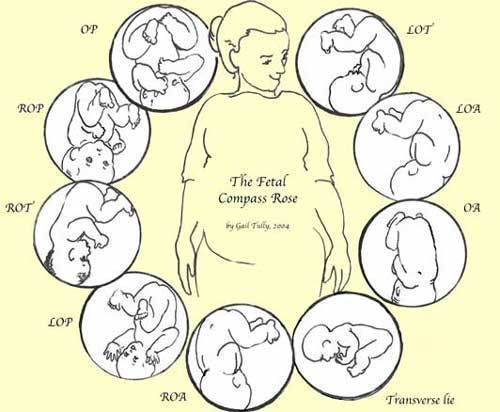

You will hear your doctor state your baby’s position and that will usually consist of 3 letters, but what do they mean? Let’s try to break this down!

L or R

Meaning Left (L) or Right (R) and referring to which side of your uterus your baby’s back is up against.

O

Meaning Occiput (O) and referring to the back of your baby’s head.

A, P, or T

Meaning Anterior (A) referring to your back, near the pubic bone, Posterior (P) referring to your front, near the abdomen or Transverse (T) referring to halfway between Anterior and Posterior.

LOA or ROA

Left Occiput Anterior or Right Occiput Anterior.

LOP or ROP

Left Occiput Posterior or Right Occiput Posterior. These two variations are sometimes referred to as sunny side up.

LOT or ROT

Left Occiput Transverse or Right Occiput Transverse.

ASYNCLITIC

Asymmetrical. Baby head is tipped towards one shoulder.

OBLIQUE

Diagonal. Baby’s head is in the mother’s hip.

TRANSVERSE LIE

Horizontal. Baby is side-lying.

The Left Occiput Anterior (LOA) is known as the most optimal position for birth because it is one of the positions to help baby be in the smallest diameter to fit the pelvis. The crown of the LOA baby’s head most often enters the pelvis first, tucking the chin which helps the baby fit in a way that the baby’s head can mold/shape most effectively. The baby’s back can curve most effectively in this position as well. The baby slides down the softening abdomen to enter the brim. (https://www.spinningbabies.com)